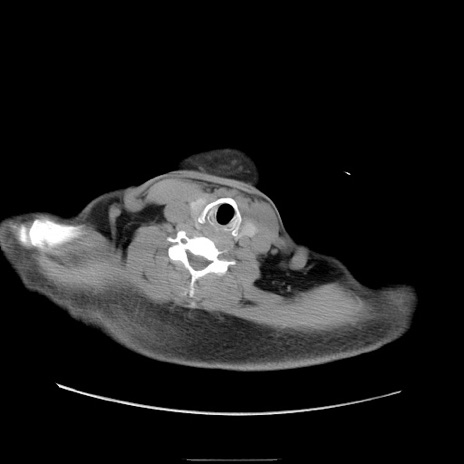

冠状断像

【症例】50歳代男性

【主訴】腹痛

【現病歴】AVMからの被殻出血のため回復期リハ病棟入院中。 本日午後3時頃急に下腹部痛が出現した。

【既往歴】AVM、被殻出血、虫垂炎、高血圧

【身体所見】意識晴明、左半身不全麻痺、会話の理解は良好、36.5°C、腹部:膨隆、全体に板状硬、下腹部正中に圧痛点あり、反跳痛-、筋性防御不明、右下腹部にope scar

【データ】WBC 9400、CRP 0.06